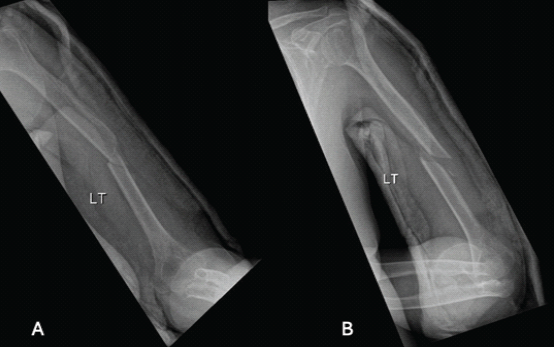

A 68-year-old right-hand dominant female presented after a fall with an isolated closed left spiral humerus fracture at the junction of the proximal ⅔ and distal ⅓ (Fig. 1).

Figure 1: Humerus fracture upon presentation after coaptation splint application, (a) showing anterior-posterior view, (b) showing lateral view.